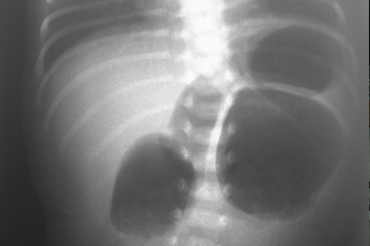

Atresia Intestinal

Inicio Neonatal y Lactante

Neo Natal y Lactante